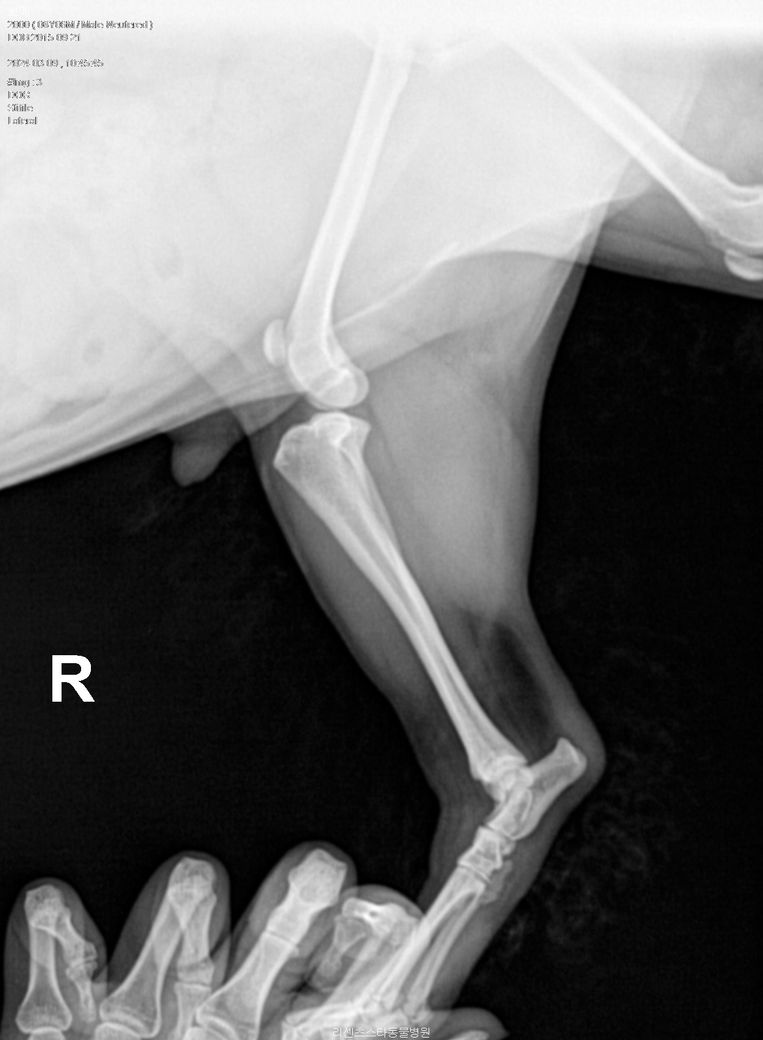

인대파열인가요?(엑스레이 판독 부탁드립니다)

어제 소파위에서 이리저리 뛰어 다니다 갑자기 소리를 내며 왼쪽 다리에 고통을 느끼는 것 같았습니다. 하루가 지난 지금도 왼쪽 뒷 다리는 계속 들고 다닙니다. 만졌을때 고통스러워 하지는 않습니다.

동네 병원에서 엑스레이를 찍었는데 인대 파열이 의심 된다고 합니다. 엑스레이 자료를 주시면서다른 전문 병원으로 가라고 하시네요. 여기 전문가선생님들께서 엑스레이 자료를 보시고 의견을 주셨으면 좋겠습니다

아픈 쪽 다리는 왼쪽 뒷 다리(L) 사진입니다

방사선 촬영만으로는 십자인대 단열을 확진할 수는 없겠지만 지금 왼쪽 다리를 보시면 아예 정강 뼈가 전방으로 변위가 심한 것을 보면 십자인대 완전 단열을 가능성이 매우 큽니다.

이런 경우는 재활 치료나 무릎 보호대만으로는 치료가 거의 불가능 할 수도 있으며 수술을 빨리 하지 않는 경우에는 퇴행성 변화가 굉장히 빨리 일어나서.

추후 수술을 한다 하더라도 회복이 느리거나 회복이 되지 않을 수도 있습니다.